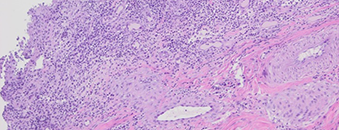

Sinds een paar dagen slecht eten, bloederige diarree, drinkt wel. De pup vertoonde opvallend gele slijmvliezen, en geelverkleuring van de organen en weefsels passend bij icterus.